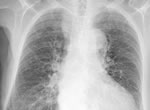

Проходил флюорографию и доктор написал, что подозрение на приконюрневую пневмонию.

Терапевт, сказала, что возможно это хронический бронхит.